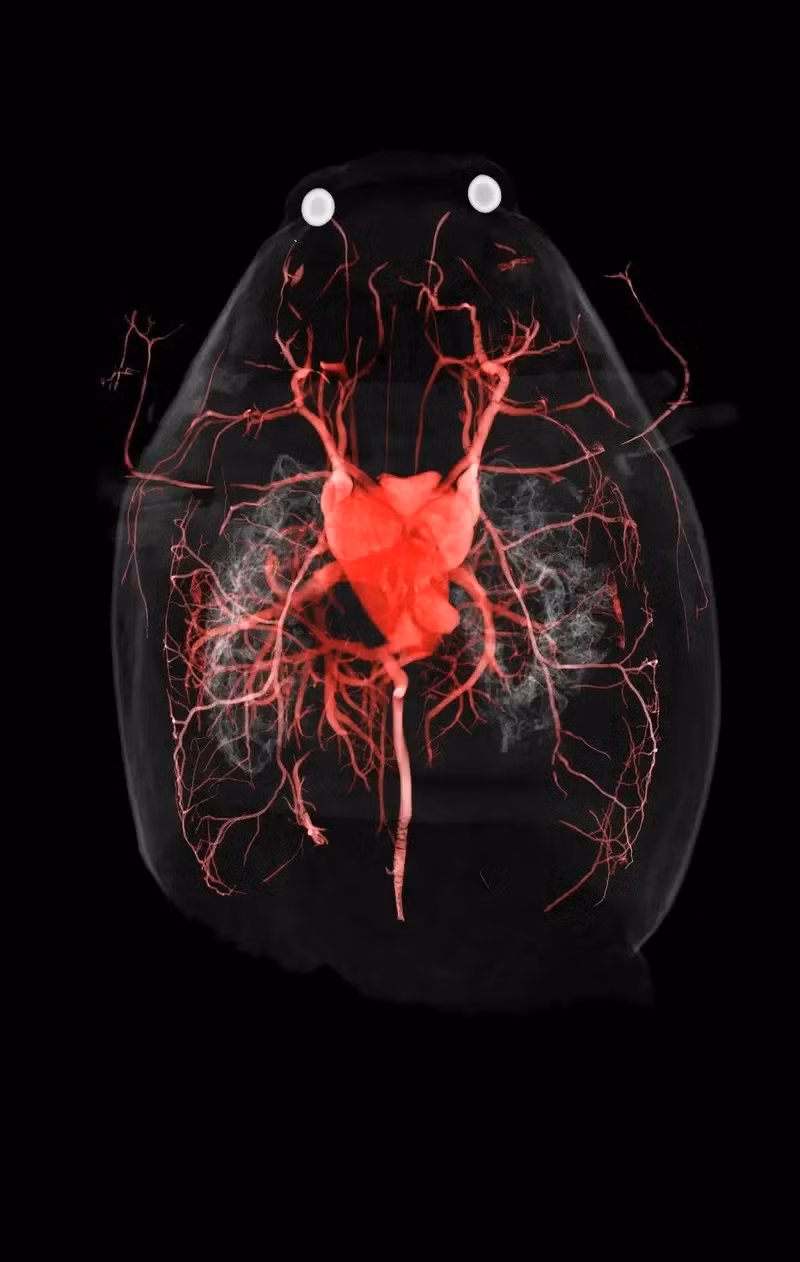

Ếch cừu: Điểm độc đáo của theo dõi này là hệ thống mạch máu của ếch cừu phương bắc, với điểm nhấn là trái tim chiếm phần lớn diện tích cơ thể nó.